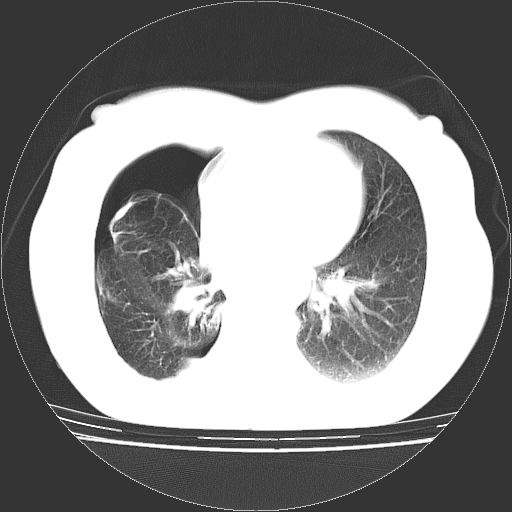

以下是引用zhangzhongshou在2008-3-22 12:52:00的发言:[br]1、右侧液气胸。[br]2、腹水。建议进一步检查。

以下是引用鲁巨ct在2008-3-22 14:10:00的发言:[br]1、右侧液气胸,右中下叶节段性不张。[br]2、腹水,建议上腹部ct检查

以下是引用zjzjr在2008-3-22 17:19:00的发言:[br]1、右侧液气胸,右下叶节段性不张。[br]2、腹水,建议上腹部ct检查